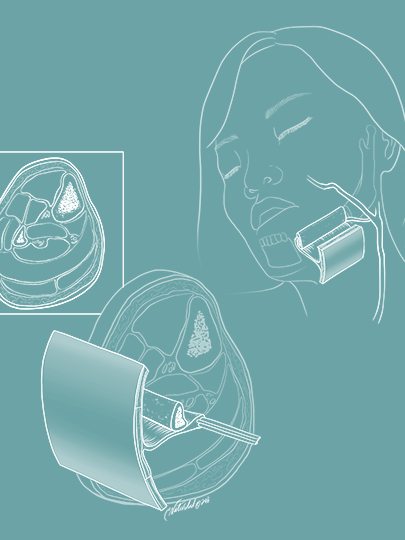

Running series of animated visual abstracts, Quick Takes, created for The New England Journal of Medicine as part of a team of illustrators, medical writers, and scientists. These short, iconographic animations aim to succinctly describe clinical trials and increase the awareness and understanding of important research findings.

Adopting The Journal’s visual style and asset library, I am responsible for the entire production process including narration editing, storyboarding, layout, illustration, and animation.